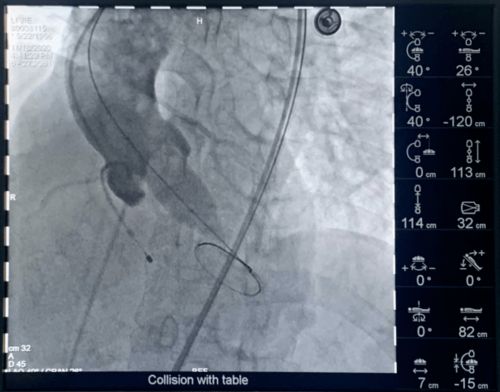

心血管重构是指心血管系统在病理或生理状态下发生的结构、功能和代谢的适应性或病理性改变过程。根据重构性质可分为正性重构(代偿性扩张)和负性重构(病理性收缩),其中心血管负性重构特指血管或心脏在疾病状态下出现的管腔狭窄、室壁增厚等恶化性改变。

负性重构是心血管疾病恶化的关键环节,需通过药物(如ACE抑制剂、β受体阻滞剂)或手术干预以延缓进展。例如,冠状动脉负性重构会加速心绞痛发作,而心室负性重构则增加心力衰竭风险。